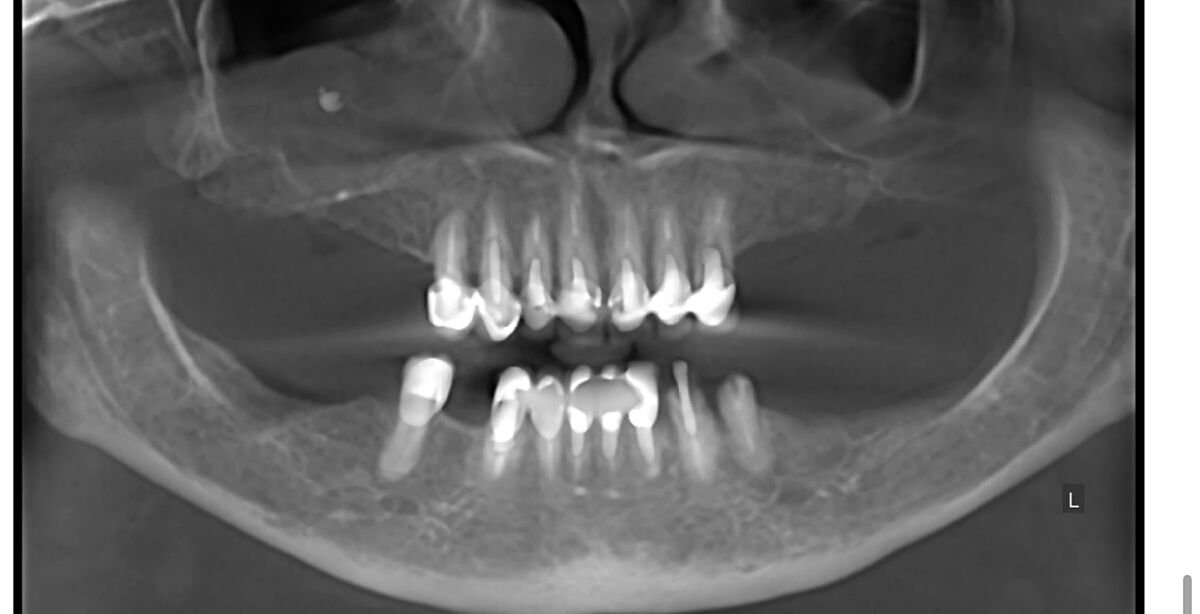

Виривати всі зуби і ставити імпланти? Тут є стоматологи оцінити їх по знімку?

В 70 років приживуться імпланти? Ви суму можете уявити. На знімках канали і корені зубів нормальні, проліковані. Запалень нема. Простіше поміняти старі коронки і поставити незйомні мости на імпланти. По два на одну сторону. Або в такому віці можна дешевий протез, що до ясен прилипає, типу резиновий. Кожні два роки міняти.

Хоч і на штифтах, але корені нормальні, коронка зуба проглядується. У вас навіть прикус правильний при відсутності бокових зубів зверху і знизу. Відстань між щелепами де пусті місця по боках прям ідеально симетричні і не сильно просіли.

Есть здесь зубы нормальные. Есть под вопросом. Т.к. этот снимок надо смотреть полноценно , а не скрины с него. Здесь могут быть и срезы неудачные, и не всегда понятно - артефакты это или на самом деле это есть. + замеры делать надо. И это только рентгенологически... Иногда составляются планы с удалением относительно нормальных зубов для экономии средств и снижения травматичности операции...